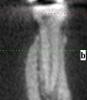

В клинике говорят, что зуб "плохой", нечего его жалеть. Между корнями кости нет, скорее всего, киста. На мой вопрос, а что будет вместо зуба - говорят, дырка будет, ничего ставить туда не надо.

Советую удалить... я сторонник "спасать" зубы но не этот... обратитесь к грамотному хирургу возможна ли одномоментная подсадка костной ткани (клинику не вижу не буду вдаваться в подробности). Если нет то удаление+костный блок+имплант. Это возможно если нет тяжелых хронических заболеваний.